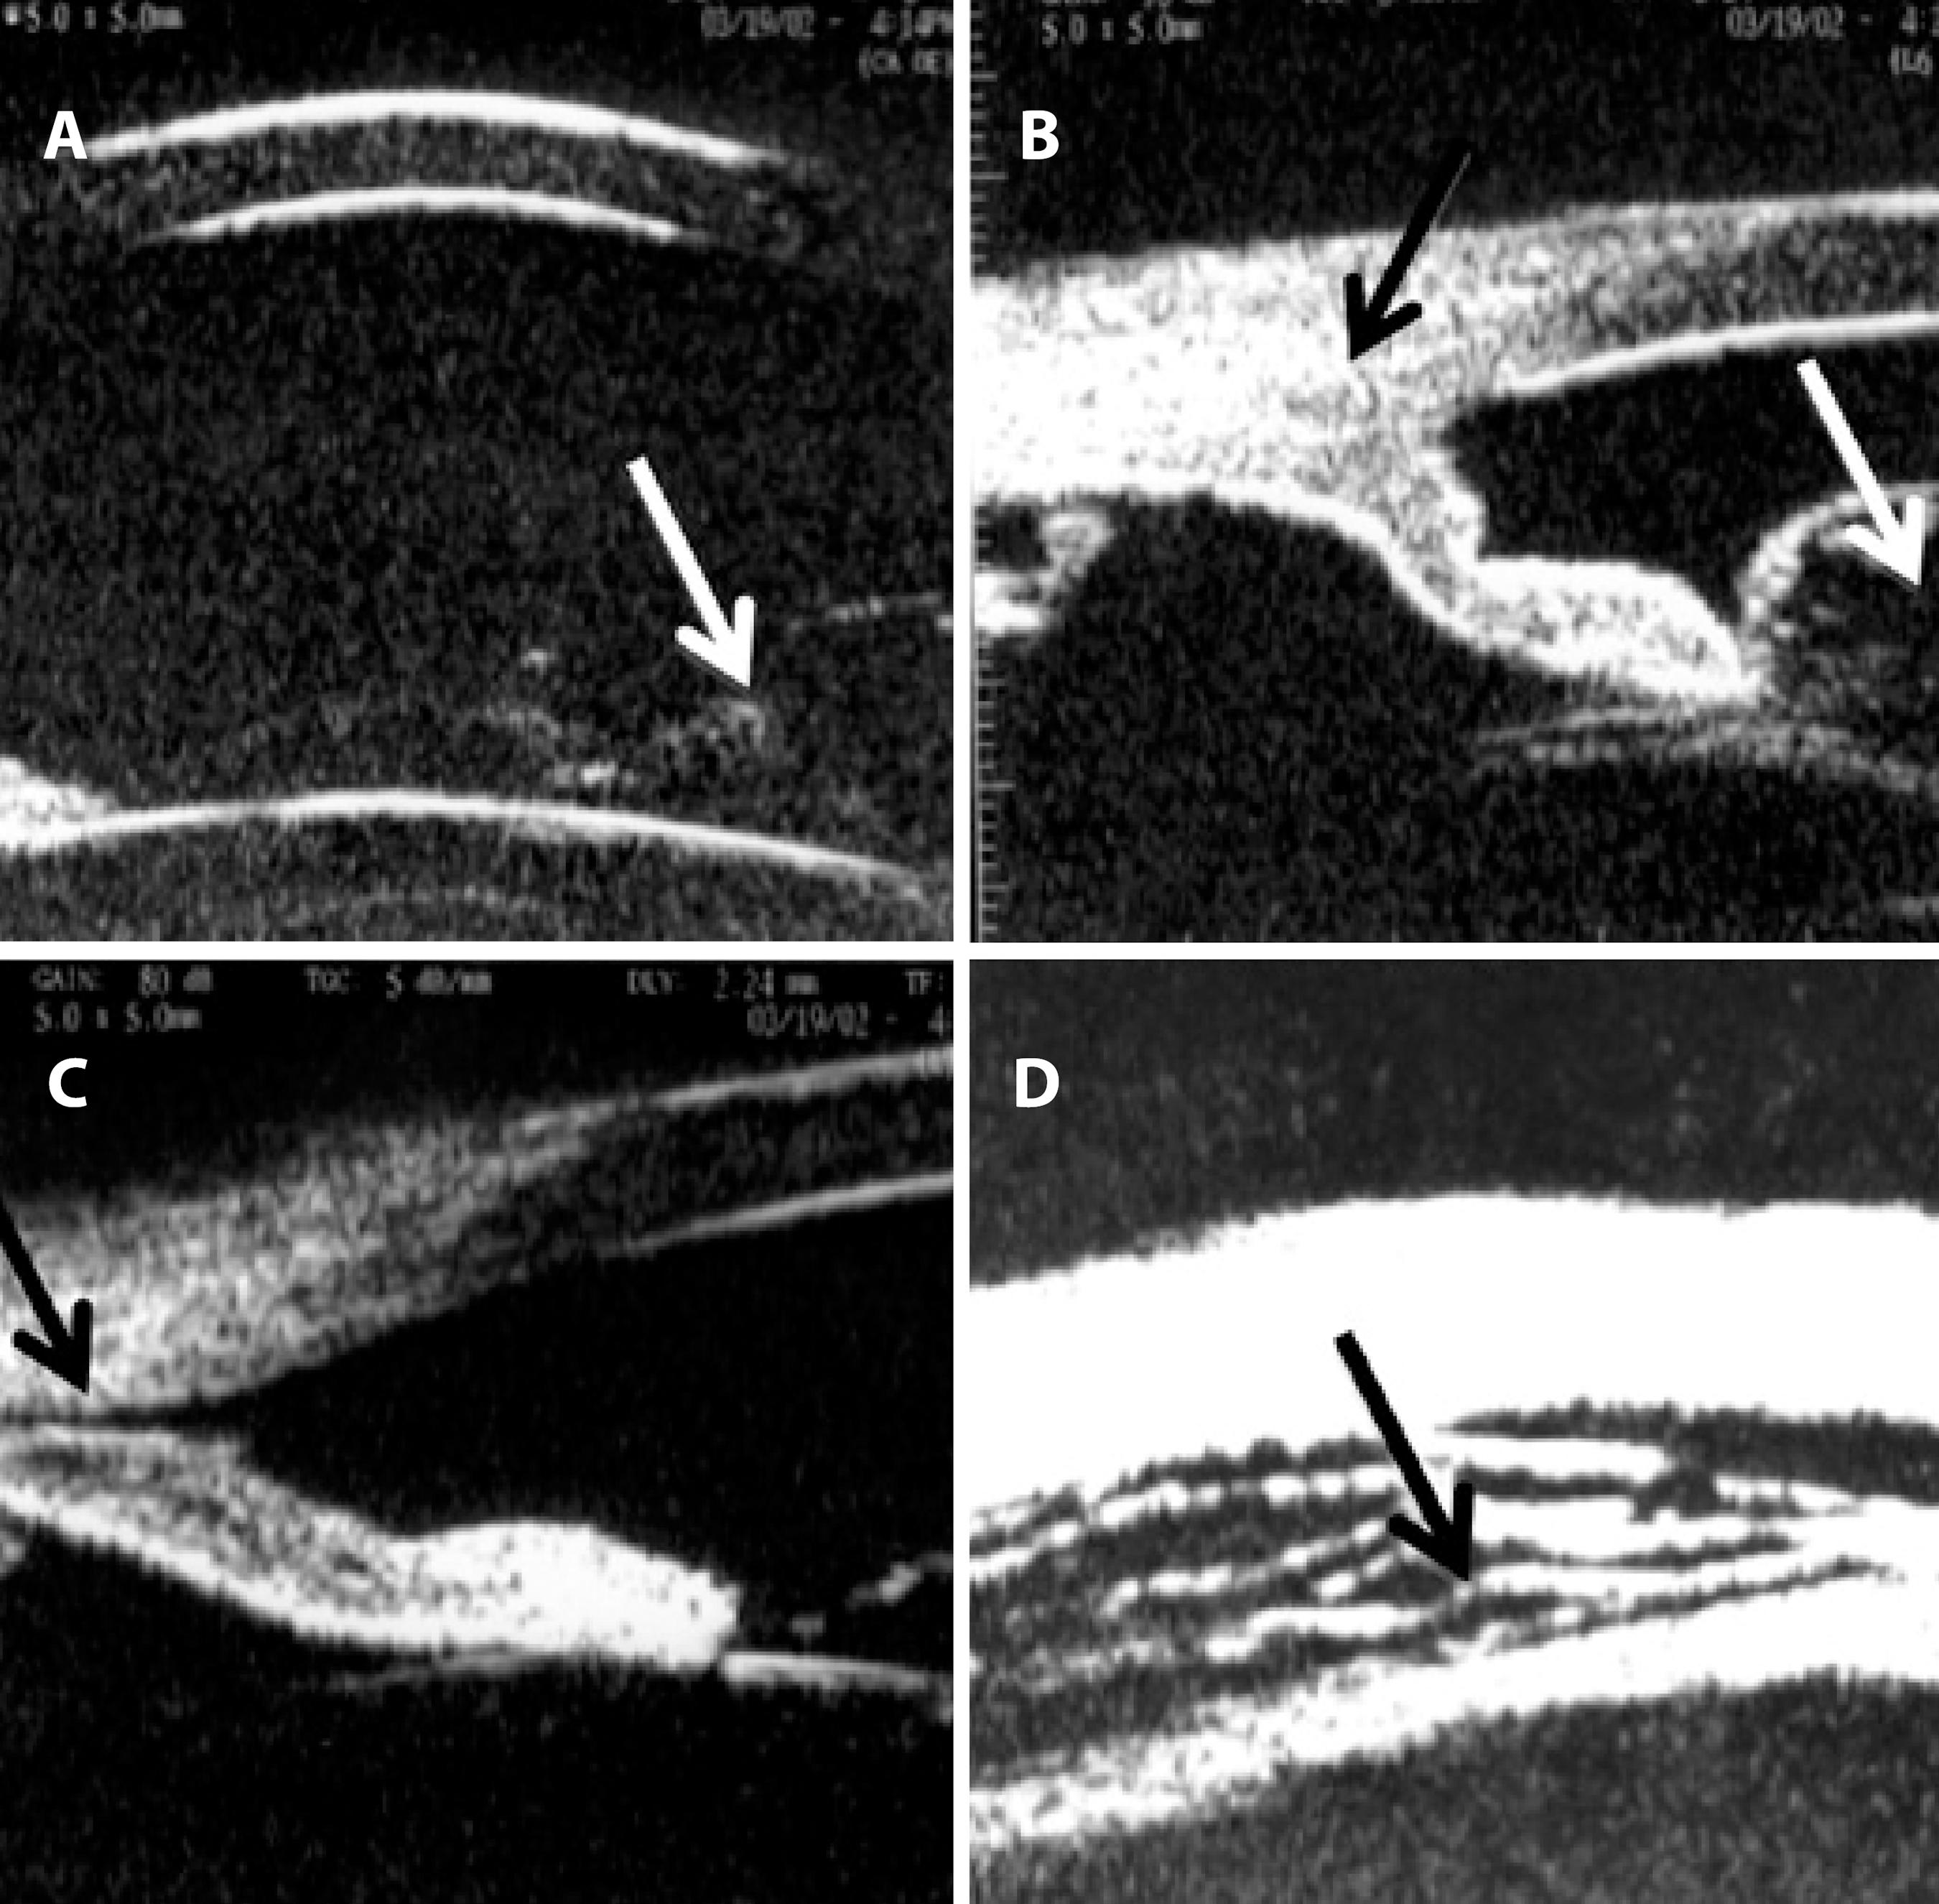

B-scan, 10-MHz ultrasonography revealed superior peripheral choroidal detachment (10 o'clock to 2 o'clock position), an attached retina, optic disc edema, and choroidal thickening (Figure 1B). UBM (50-MHz immersion technique) revealed an anterior chamber depth of 3.0 mm, vitreous herniation into the anterior chamber (Figure 2A), inferior corectopia, apposition of the peripheral iris to the posterior surface of the cornea (Figure 2B), a suspected cyclodialysis cleft at the 7 o'clock position (Figure 2C), and a 360º ciliary body detachment showing a cavernous pattern of the suprachoroidal space (Figure 2D).

Figure 2 . Ultrasound biomicroscopy (UBM) performed at 50 MHz using the immersion technique after blunt trauma. A) Anterior chamber depth of 3.0 mm, vitreous herniation into the anterior chamber (arrow). B) Inferior angle demonstrating apposition of the peripheral iris (black arrow) to the posterior surface of the cornea associated with vitreous prolapse through the pupil (white arrow). C) A suspected cyclodialysis cleft (black arrow) at the 7 o’clock position. D) Ciliary body detachment (cavernous pattern of the suprachoroidal space; black arrow) in 360°.